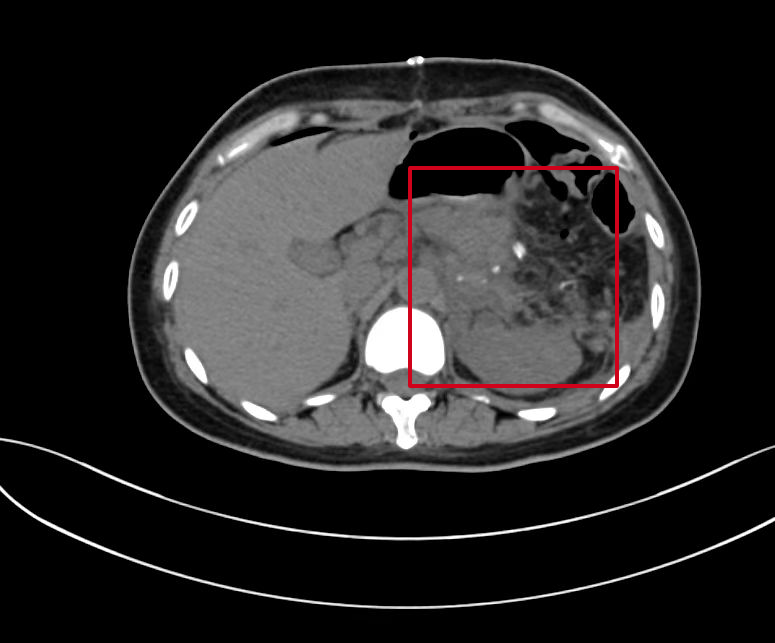

患者爲40歲左右的中年女性,因腹痛在惠州市第六人民醫院急診醫學(xué)科行腹部CT檢查後(hòu)提示胰腺腫瘤收入胃腸肝膽外科,其實患者于15年前就(jiù)已發(fā)現胰腺腫瘤的存在,當時(shí)腫瘤體積小、考慮良性可能(néng),且尚未造成(chéng)不适症狀,故一直未予以積極治療。患者入院後(hòu)完善增強CT檢查,提示胰體尾腫瘤不排除惡性腫瘤、胰源性門脈高壓、脾髒增大。

标注所示爲巨大腫瘤